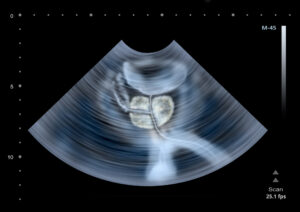

Cryoablation is performed either in a hospital or surgical center while the patient is under general anesthesia. During the procedure, the surgeon uses ultrasound imaging to guide a thin, needle-like probe into the prostate. This probe is attached to a machine that dispenses extremely cold gas. Once the probe is in place, the gas will be released to target and freeze cancerous cells. The surgeon will carefully monitor the release of gas in order to minimize damage to surrounding tissue.